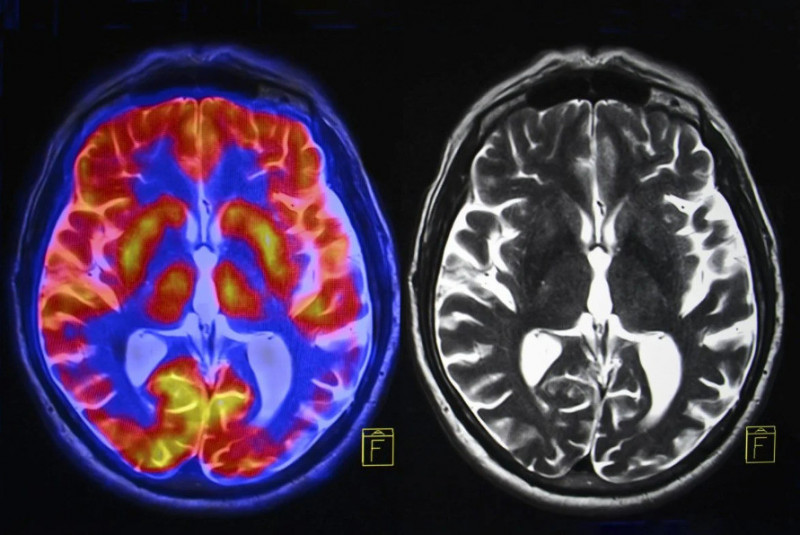

研究发现大脑的躯体认知动作网络与帕金森氏症相关,此发现可能改变巴金森氏症治疗方式。 (撷自Shutterstock)

为了验证此想法,研究团队分析了来自美国和中国800多名参与者的多种脑部影像数据。该研究纳入了接受脑深部电刺激(DBS)或非侵入性疗法(如经颅磁刺激、聚焦超音波刺激)的巴金森氏症患者。此外研究也纳入了健康志愿者和其他运动障碍患者作为对照组。